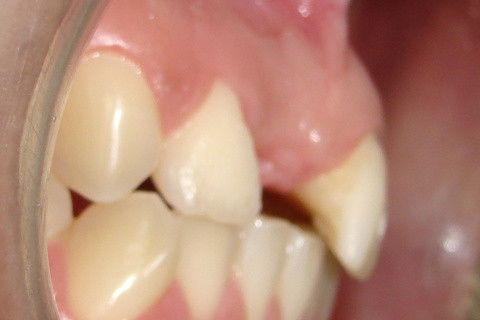

Aspecto 3 semanas após a reabertura e enxerto

Foto de perfil, mostrando a melhora no contorno dos tecidos gengivais